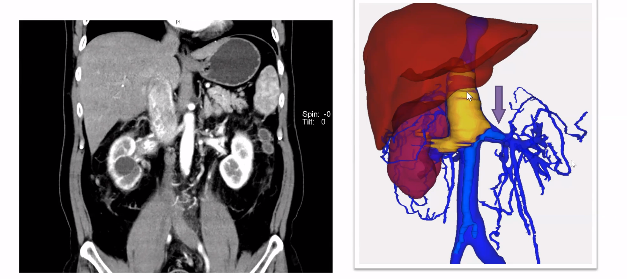

下腔静脉不一定都要阻断

对于腔静脉各端及分支的充分游离和暴露是顺利取栓的重要条件,而各支血管的完全阻断更为关键。但是,下腔静脉一定要阻断吗?既往积累经验告诉我们瘤栓上方下腔静脉完全不用阻断。如下图所示,病例患者具有肾静脉和肾上腺中央静脉双瘤栓,在手术中取肾上腺中央静脉的瘤栓时,其上方腔静脉并没有阻断,而是通过剪开腔静脉直接将瘤栓取出。取栓之后,再把静脉壁切掉,可以获得足够空间后再重新进行阻断,有利于完成后续缝合等多个操作。(备注:视频中有动态手术操作过程)